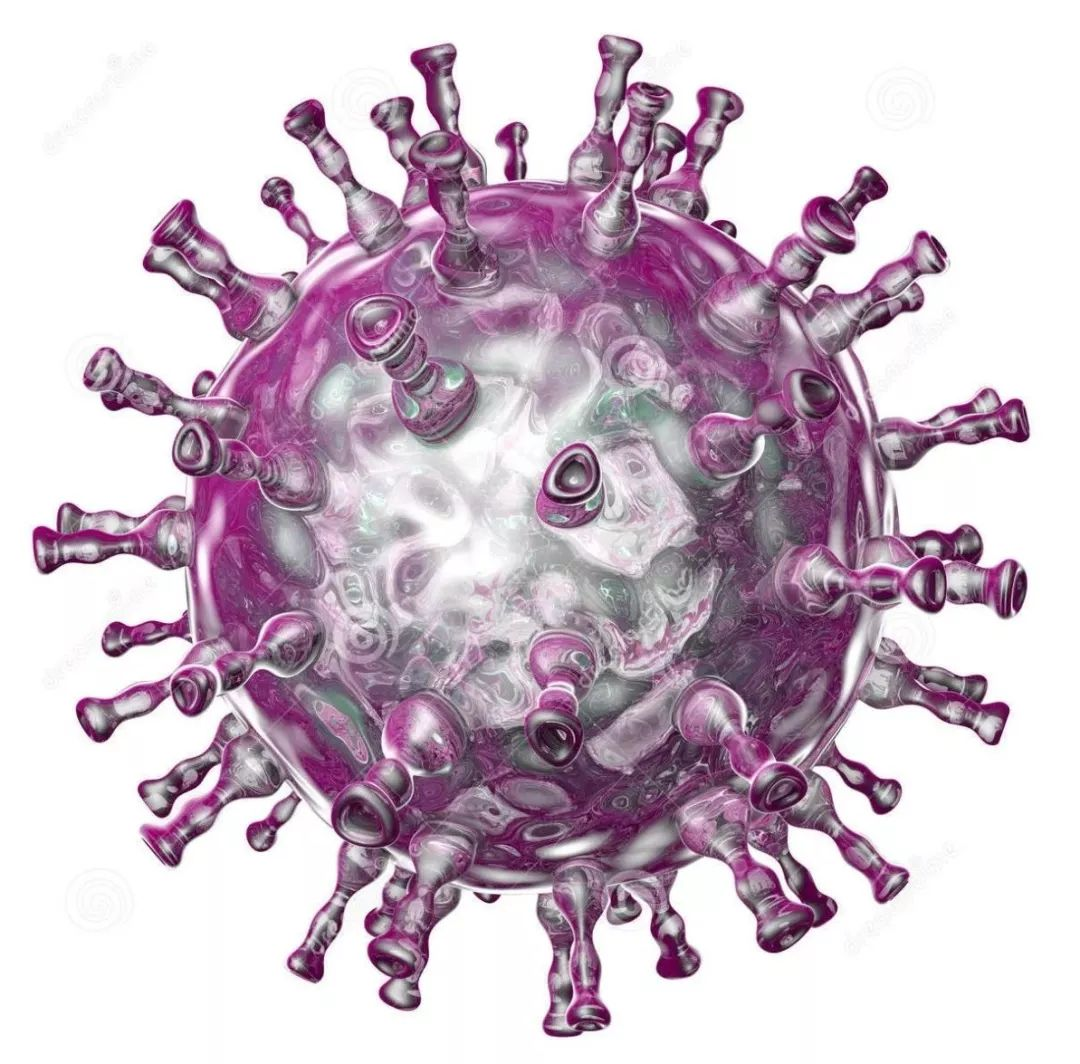

它们都是由同一种水痘-带状疱疹病毒(varicella zoster virus,简称VZV)引起的感染。而这种病毒广泛分布在全世界,人类是它唯一的宿主。

3D版的水痘-带状疱疹病毒

人类疱疹病毒

注:在医学上,人类的疱疹病毒一共有8型,分别是单纯疱疹病毒1型、单纯疱疹病毒2型、水痘-带状疱疹病毒、EB病毒、巨细胞病毒、人类疱疹病毒6型、人类疱疹病毒7型、人类疱疹病毒8型